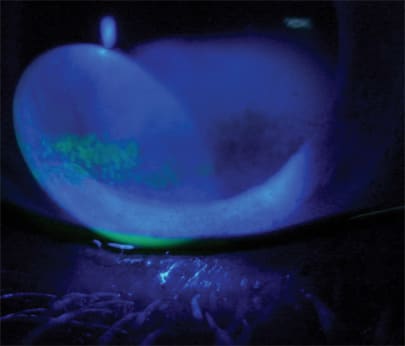

Fluorescein staining reveals severe dry eye in a Thyroid Eye Disease patient.

Thus, when dye staining of the conjunctiva or cornea is evident, a combination of corticosteroids and cyclosporine may be more effective. Our typical regimen: loteprednol 0.5% (Lote-max, B&L) q.i.d. for two weeks, with a reduction to b.i.d. dosing for an additional four to six weeks. We also employ cyclosporine b.i.d. either starting concomitantly with the steroid or after two weeks for a six-month duration, depending on the severity of symptoms.